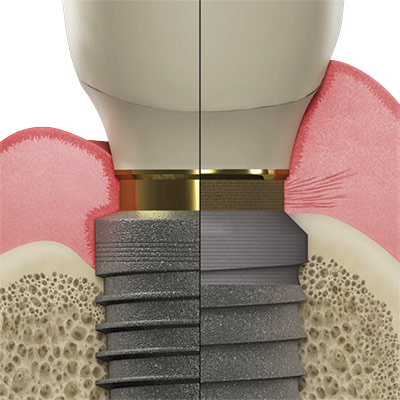

Observe 2–3 live implant surgeries showcasing immediate placement techniques in various sites using smart shape healing abutments.

Immediate implant placement offers significant clinical and operational advantages for both specialists and general dentists—especially when paired with smart shape healing abutments that support efficient healing and streamlined workflows. This course provides clinicians with the skills and knowledge to confidently plan, place, and restore immediate implants using a fully digital approach from assessment through final prosthetic delivery. Participants will explore case selection criteria, risk factors, and complication prevention strategies while gaining insight into the biological benefits of smart shape healing abutments. The program features a blend of lecture, workflow analysis, hands-on intraoral scanning, and 2–3 live surgeries demonstrating implant techniques across various clinical scenarios. By the end of the course, attendees will be equipped to integrate immediate implant placement into their practice with confidence—enhancing patient outcomes, clinical efficiency, and treatment success through modern digital protocols.

Gain the confidence to place immediate implants with precision using smart shape healing abutments and digital workflows. This immersive course offers the live training and hands-on experience you need to deliver efficient, predictable results and elevate patient care.